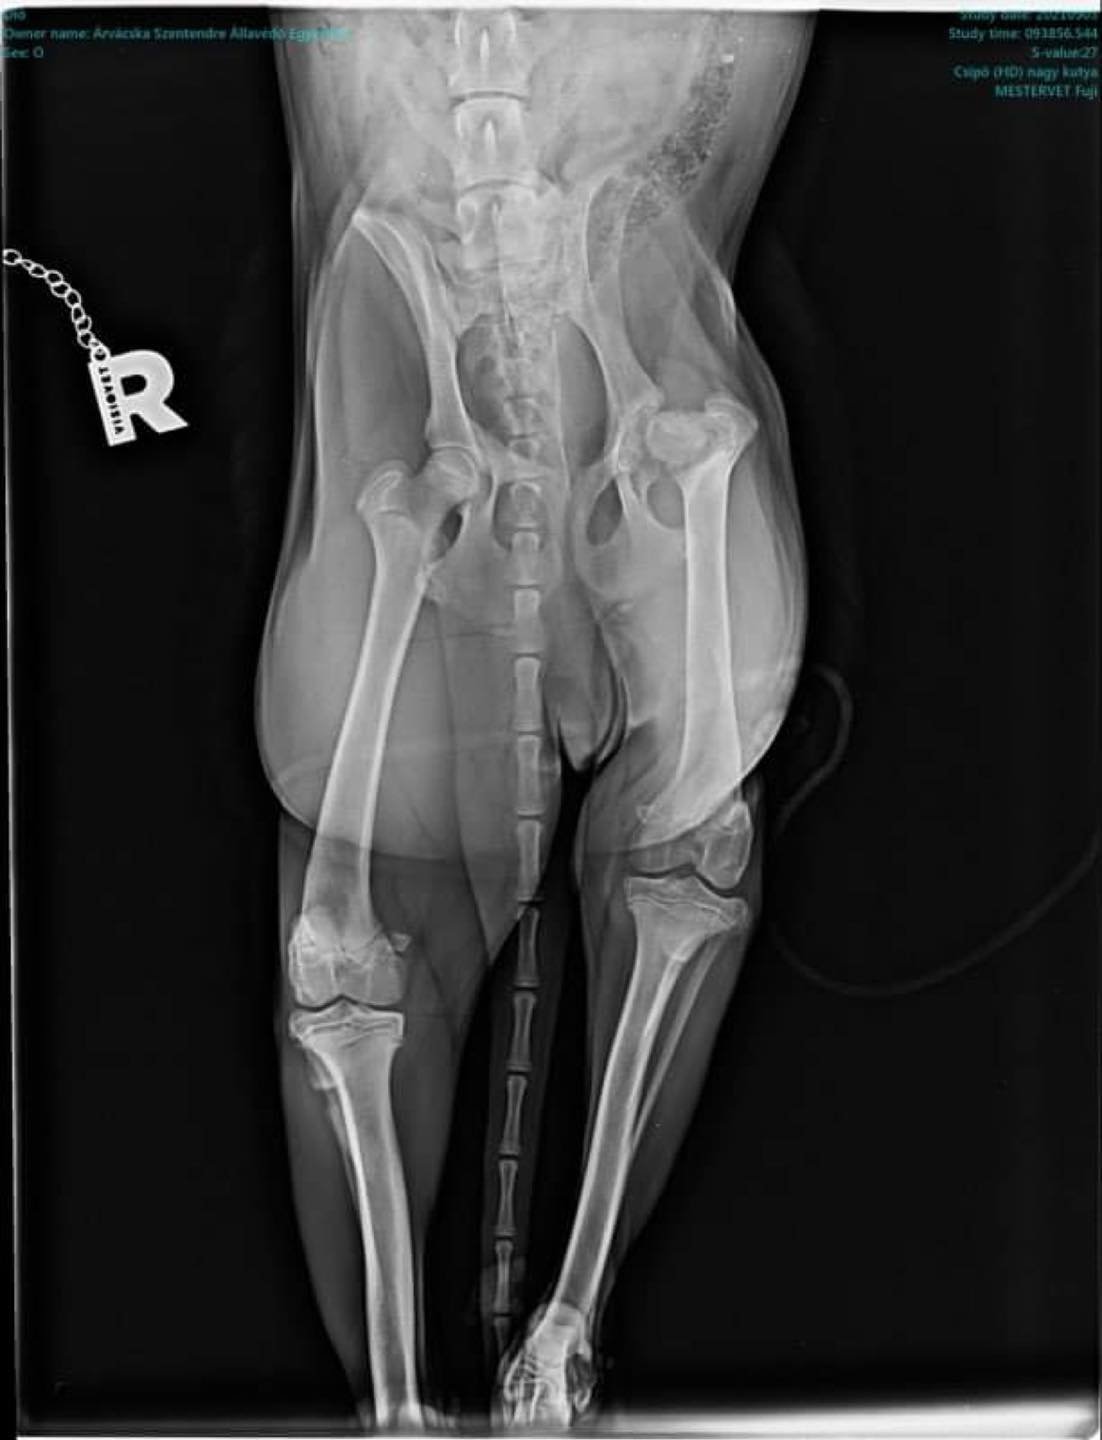

Tegnapi nap tudtunk meg, hogy Dió kutyusunkat meg kell műteni, mert combnyaktörése volt, és a fájdalommentes élethez minél előbb segítségre van szüksége.

A műtét után fikoterápiára kell hordani, mert a megrövidült kis lábát nyújtani szükséges.